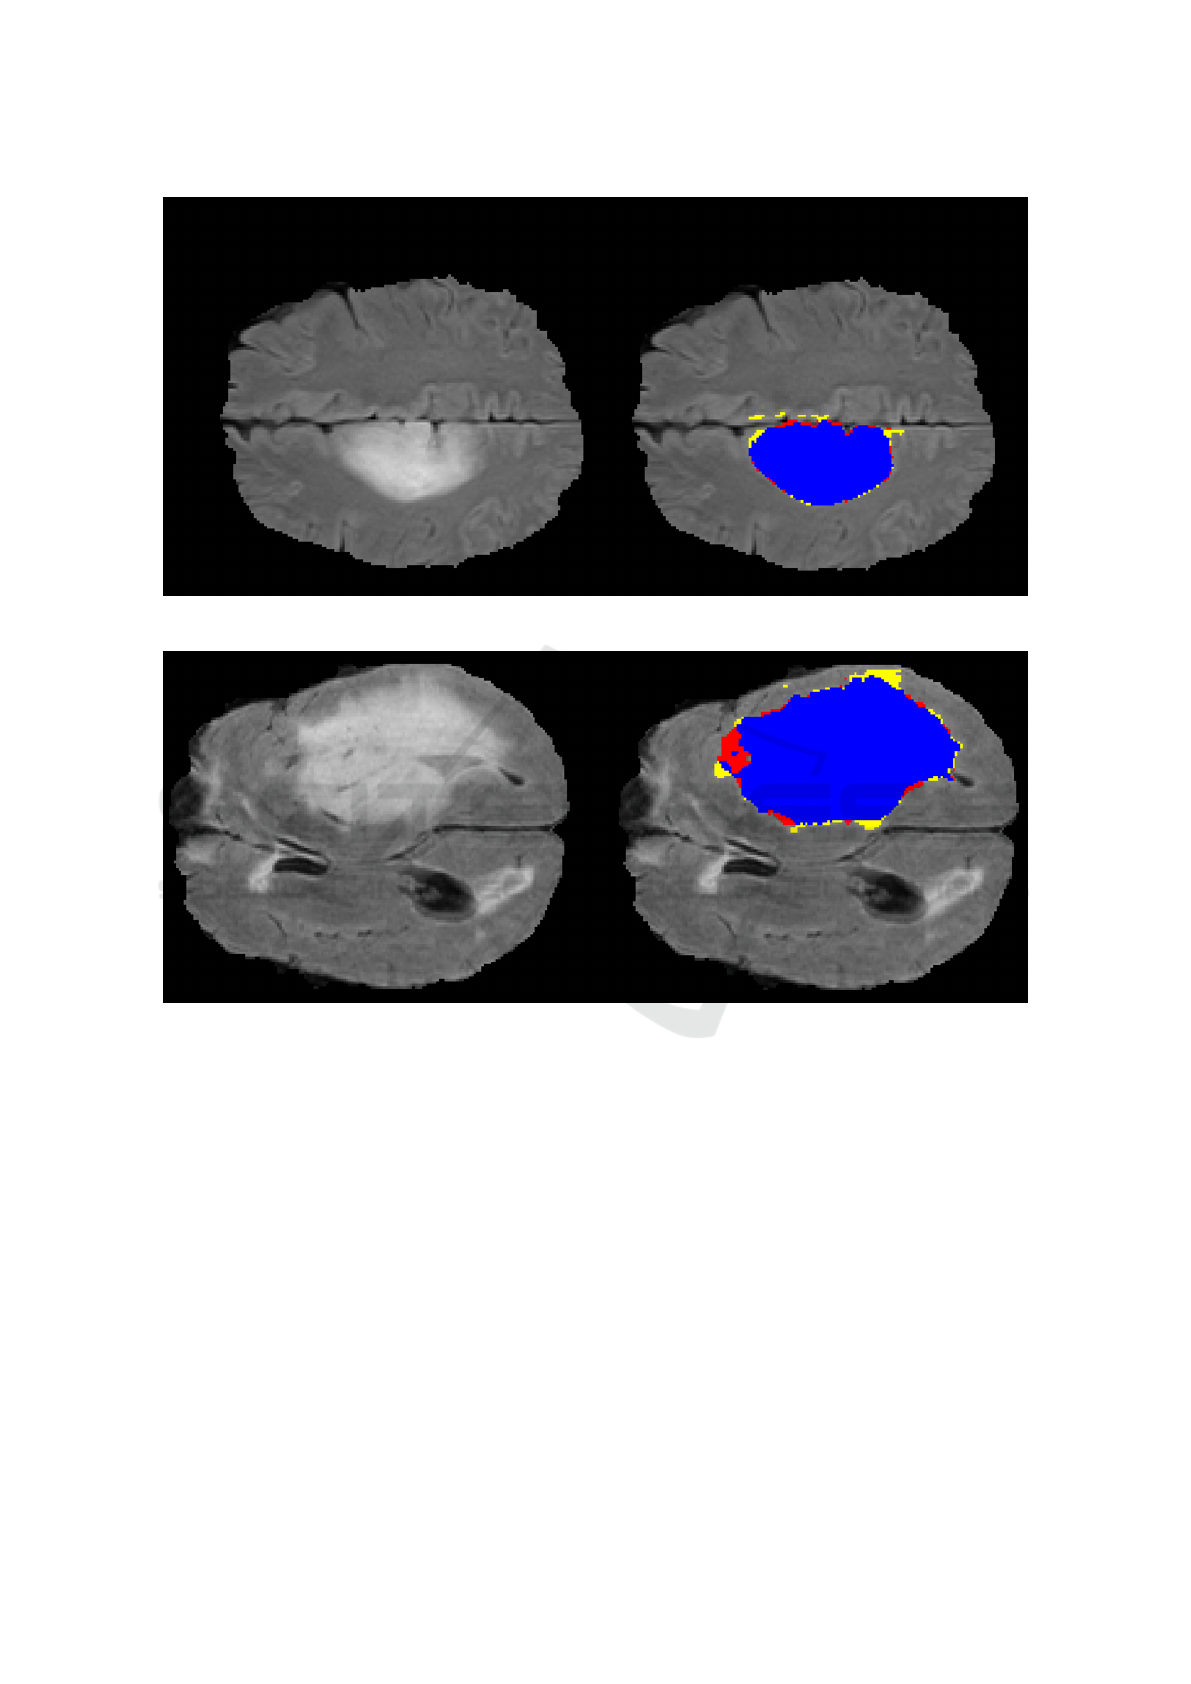

classified. The largest connected component is then

selected, representing the final result of the segmenta-

tion process.

The proposed method was used to perform “whole”

tumor segmentation of low-grade glioma tumors on

tridimensional T2-weighted FLAIR images. These

images, as well as the ground truth information, were

extracted from the 2015 Multimodal Brain Tumor

Image Segmentation Benchmark (BRATS) challenge

database, which is the largest public dataset of its

type, containing a great variety of cases. All of them

were preprocessed in order to homogenize the data

and remove the skulls, guaranteeing anonymization

of the patients (Menze et al., 2015). Two images from

the original database were excluded since the assump-

tion that the largest component represents the tumor

did not hold for them, resulting in a total of 42 test

cases.